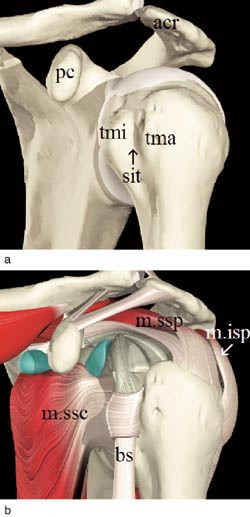

En god forståelse av de anatomiske forholdene er avgjørende for vellykket bruk av diagnostisk ultralyd. Viktige navigasjonspunkter for undersøkeren på skulderskjelettet er processus coracoideus, acromion og sulcus intertubercularis på fremsiden av humerus mellom tuberculum majus og minus (fig 1a). Viktige referansepunkter i bløtdelsapparatet er rotatorcuffen og den lange bicepssenen. Rotatorcuffen dannes av fire muskler; musculus subscapularis på fremsiden av glenohumeralleddet, musculus supraspinatus oppad, musculus infraspinatus oppad og baktil og musculus teres minor nedad og baktil. Musklene har sine utspring på scapula, løper sammen i en senemansjett (rotatorcuff) rundt caput humeri og fester seg på tuberculum majus og minus (fig 1b).

Den lange bicepssenen forløper fra sitt utspring på tuberculum supraglenoidale først intraartikulært svarende til rotatorintervallet. Ned i sulcus intertubercularis følges den av en synovial utposning av leddkapselen (fig 1b). Bursa subacromialis/subdeltoidea ligger i sjiktet mellom rotatorcuffen og musculus deltoideus. Den er normalt atskilt fra glenohumeralleddet.

Figurene 2b, 3b, 4c, 5b, 6b, 8a og b er tatt med et Siemens Sonoline Antares ultralydapparat med 11,4 MHz lydhode, figurene 2b og 5b i tillegg med teknikk for utvidet bildefelt (extended field of view). Resten av ultralydbildene er tatt med et Siemens Sonoline Sienna ultralydapparat med 7,5 MHz lydhode. Figurene 1a, 1b, 2a, 3a, 4b, 5a og 6a er gjengitt med tillatelse fra Primal Pictures Ltd (). e-fig 3, e-fig 6, e-fig 11, e-fig 12 og e-fig 13 finnes i artikkelen på www.tidsskriftet.no